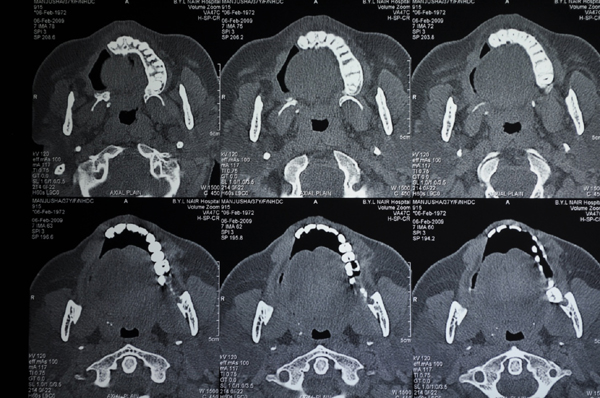

C T SCAN AXIAL SECTION SHOWS EXTENT OF DISEASE

C T SCAN CORONAL AND AXIAL SECTION SHOWS EXTENT OF DEFECT AFTER RESECTION